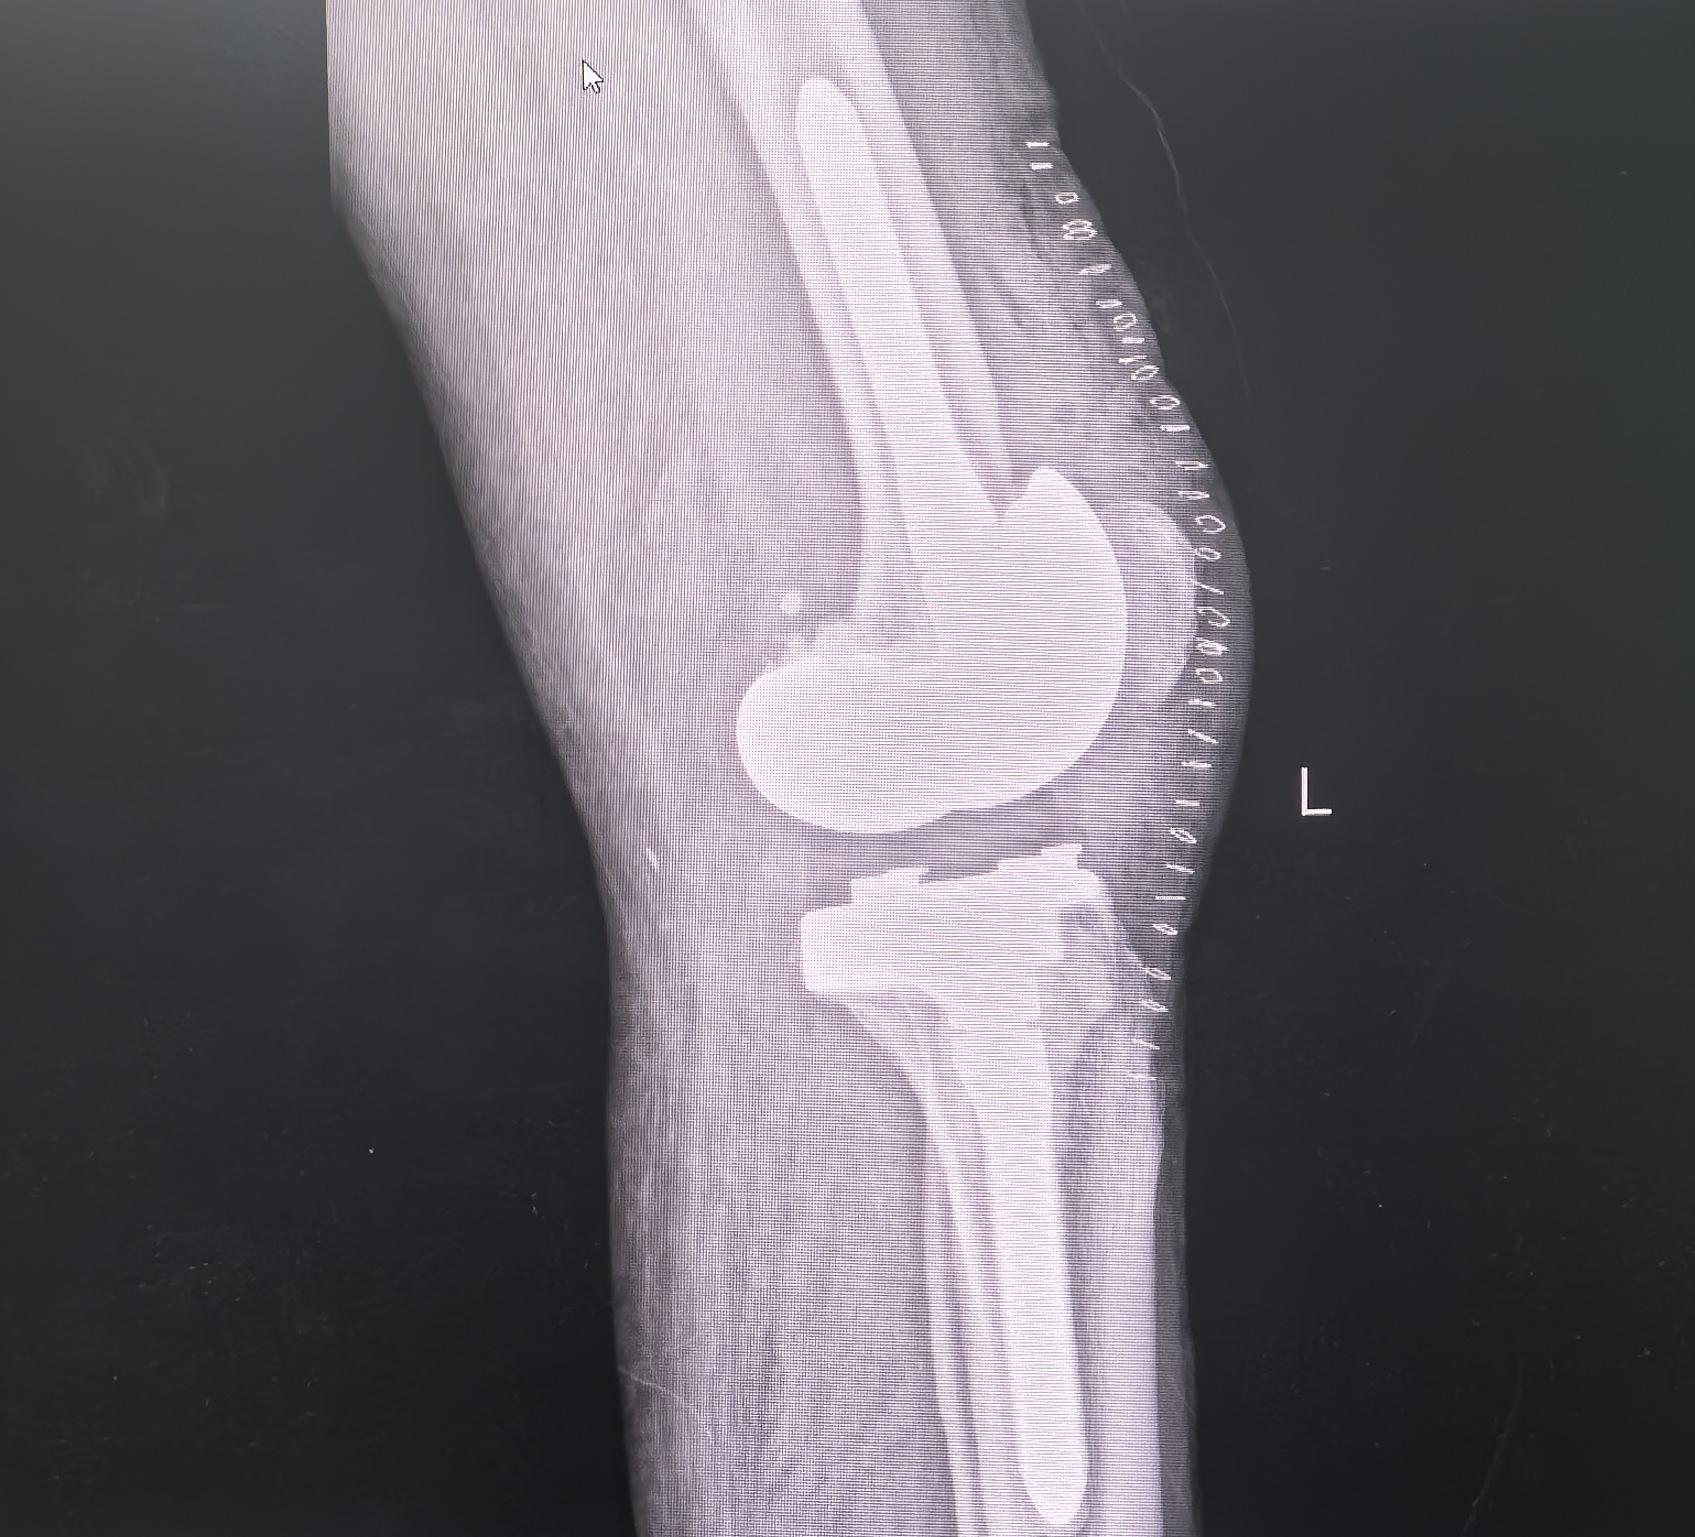

膝关节翻修。80岁老爷子,膝关节置换术后假体松动,一期翻修,再次续命20年🌹